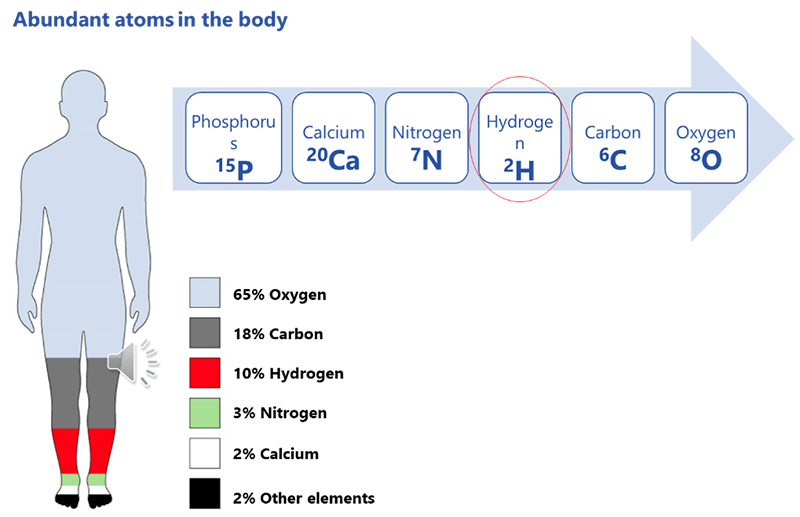

In order for MRI to work, we need to have something to image. Recall that the protons in the body spin, creating a tiny electromagnetic force. Theoretically, we could image ANY proton in the body, however, if they are not in abundance they will give off a very little signal. The more protons of the same element, the more signal will be created. The most abundant atoms in the human body are, in order starting with most abundant are: Oxygen, Carbon, Hydrogen, Nitrogen, Calcium and Phosphorus.

Recall also, that the atom of choice MUST have an odd number of protons. In examining the number of protons for each, we see that Oxygen has 8 – that is an even number, so it cannot be used. Next is Carbon, with 6 protons, so that cannot be used.

Hydrogen only has 1. 1 is an odd number. Note that Nitrogen with 7 and Phosphorus with 15 are also odd numbers, but they are not as abundant in the body. Please remember, that is the atom that has to be abundant, not the number of protons. It just has to be an odd number of protons. Why is hydrogen so abundant?

Consider the fact that the human body is more than 65% water. All tissue has some amount of water in it. Take the fat cell for instance, it is made of 80% water. The water molecule has two hydrogen atoms for every 1 oxygen atom – that’s why it’s H2O, right?